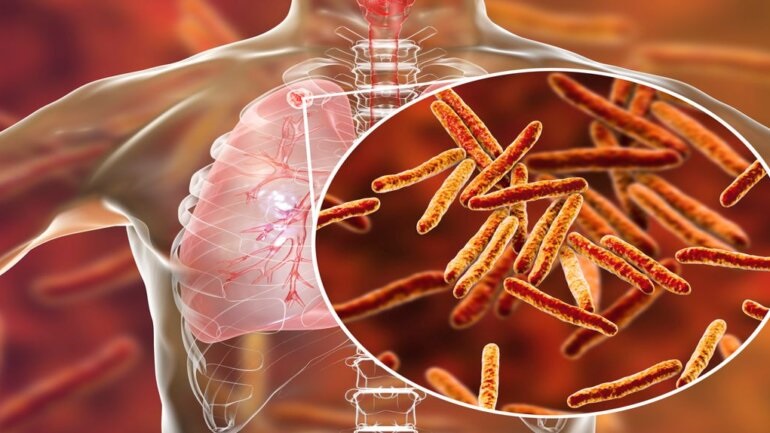

Αυξάνεται ο αριθμός των νεκρών από φυματίωση στη Ευρώπη σύμφωνα με τον ΠΟΥ

Έπειτα από δύο δεκαετίες συνεχούς υποχώρησης, ο αριθμός των νεκρών από φυματίωση αυξάνεται και πάλι στην Ευρώπη, προειδοποίησε...